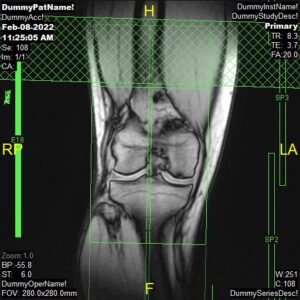

T2 Sagittal ISO

Parameters

Sample Image